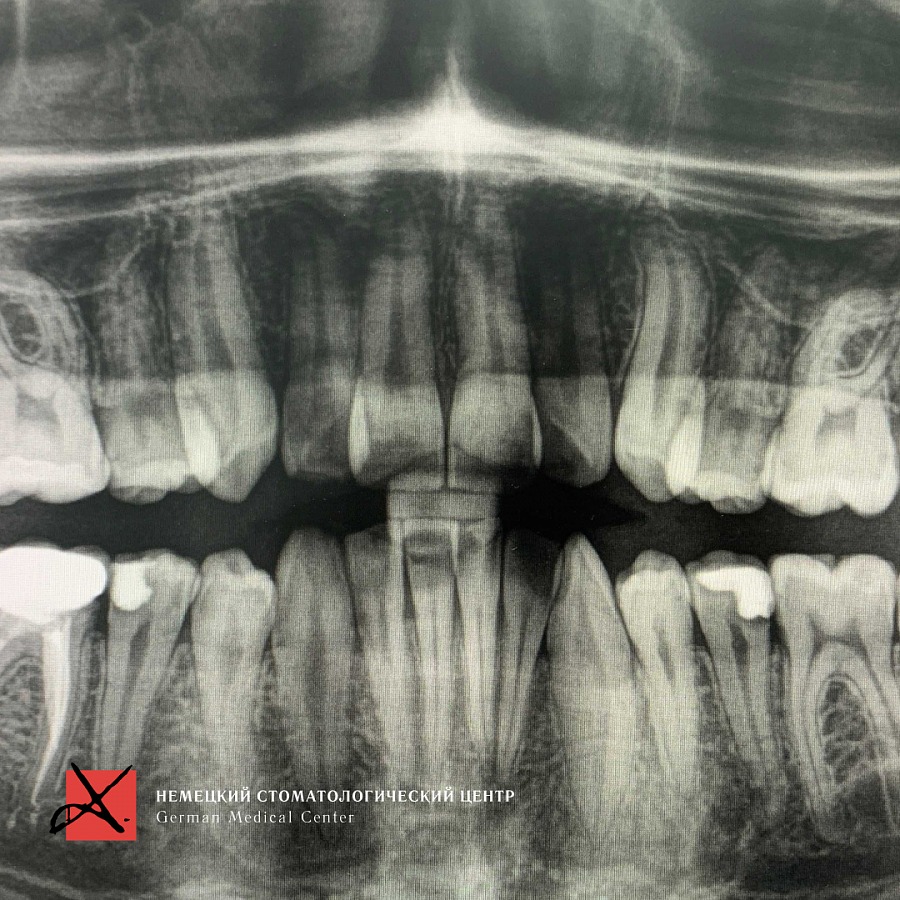

Пациент направлен стоматологом-терапевтом с целью удаления восьмерки зуба мудрости слева внизу из-за невозможности пролечить кариес между восьмым и седьмым зубом.

Восьмерка имеет наклон в горизонтальном направлении и упирается в седьмой зуб. Сложность в том, что зуб находится на нерве, и ошибки при удалении таких зубов могут привести в последствии к онемению губы и подбородка со стороны удаляемого зуба.Этапы лечения

Зуб был фрагментирован на несколько частей и удалён. После были наложены швы. Онемение не наступило.